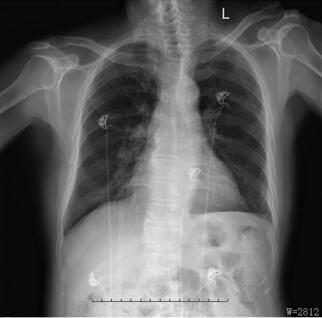

血常规:Hb:106g/L,HCT:32.5%;急诊生化:K+:5.87 mmol/L,Gl u:8.1mmol/L,Urea:19.09 mmol/L,Cr:245μmol/L;凝血:FIB:5.94g/L;BNP:384.2pg/ml;肌钙蛋白:0.159μg/L。心肌酶:肌酸激酶同工酶:31 U/L。心脏彩超:EF:25%,心脏考虑高血压并左室心肌多节段缺血性改变,左心泵血功能较差,轻度二尖瓣反流和主动脉瓣反流(二漏主漏)。胸片如图058‐1 所示。

图058‐1 胸片结果